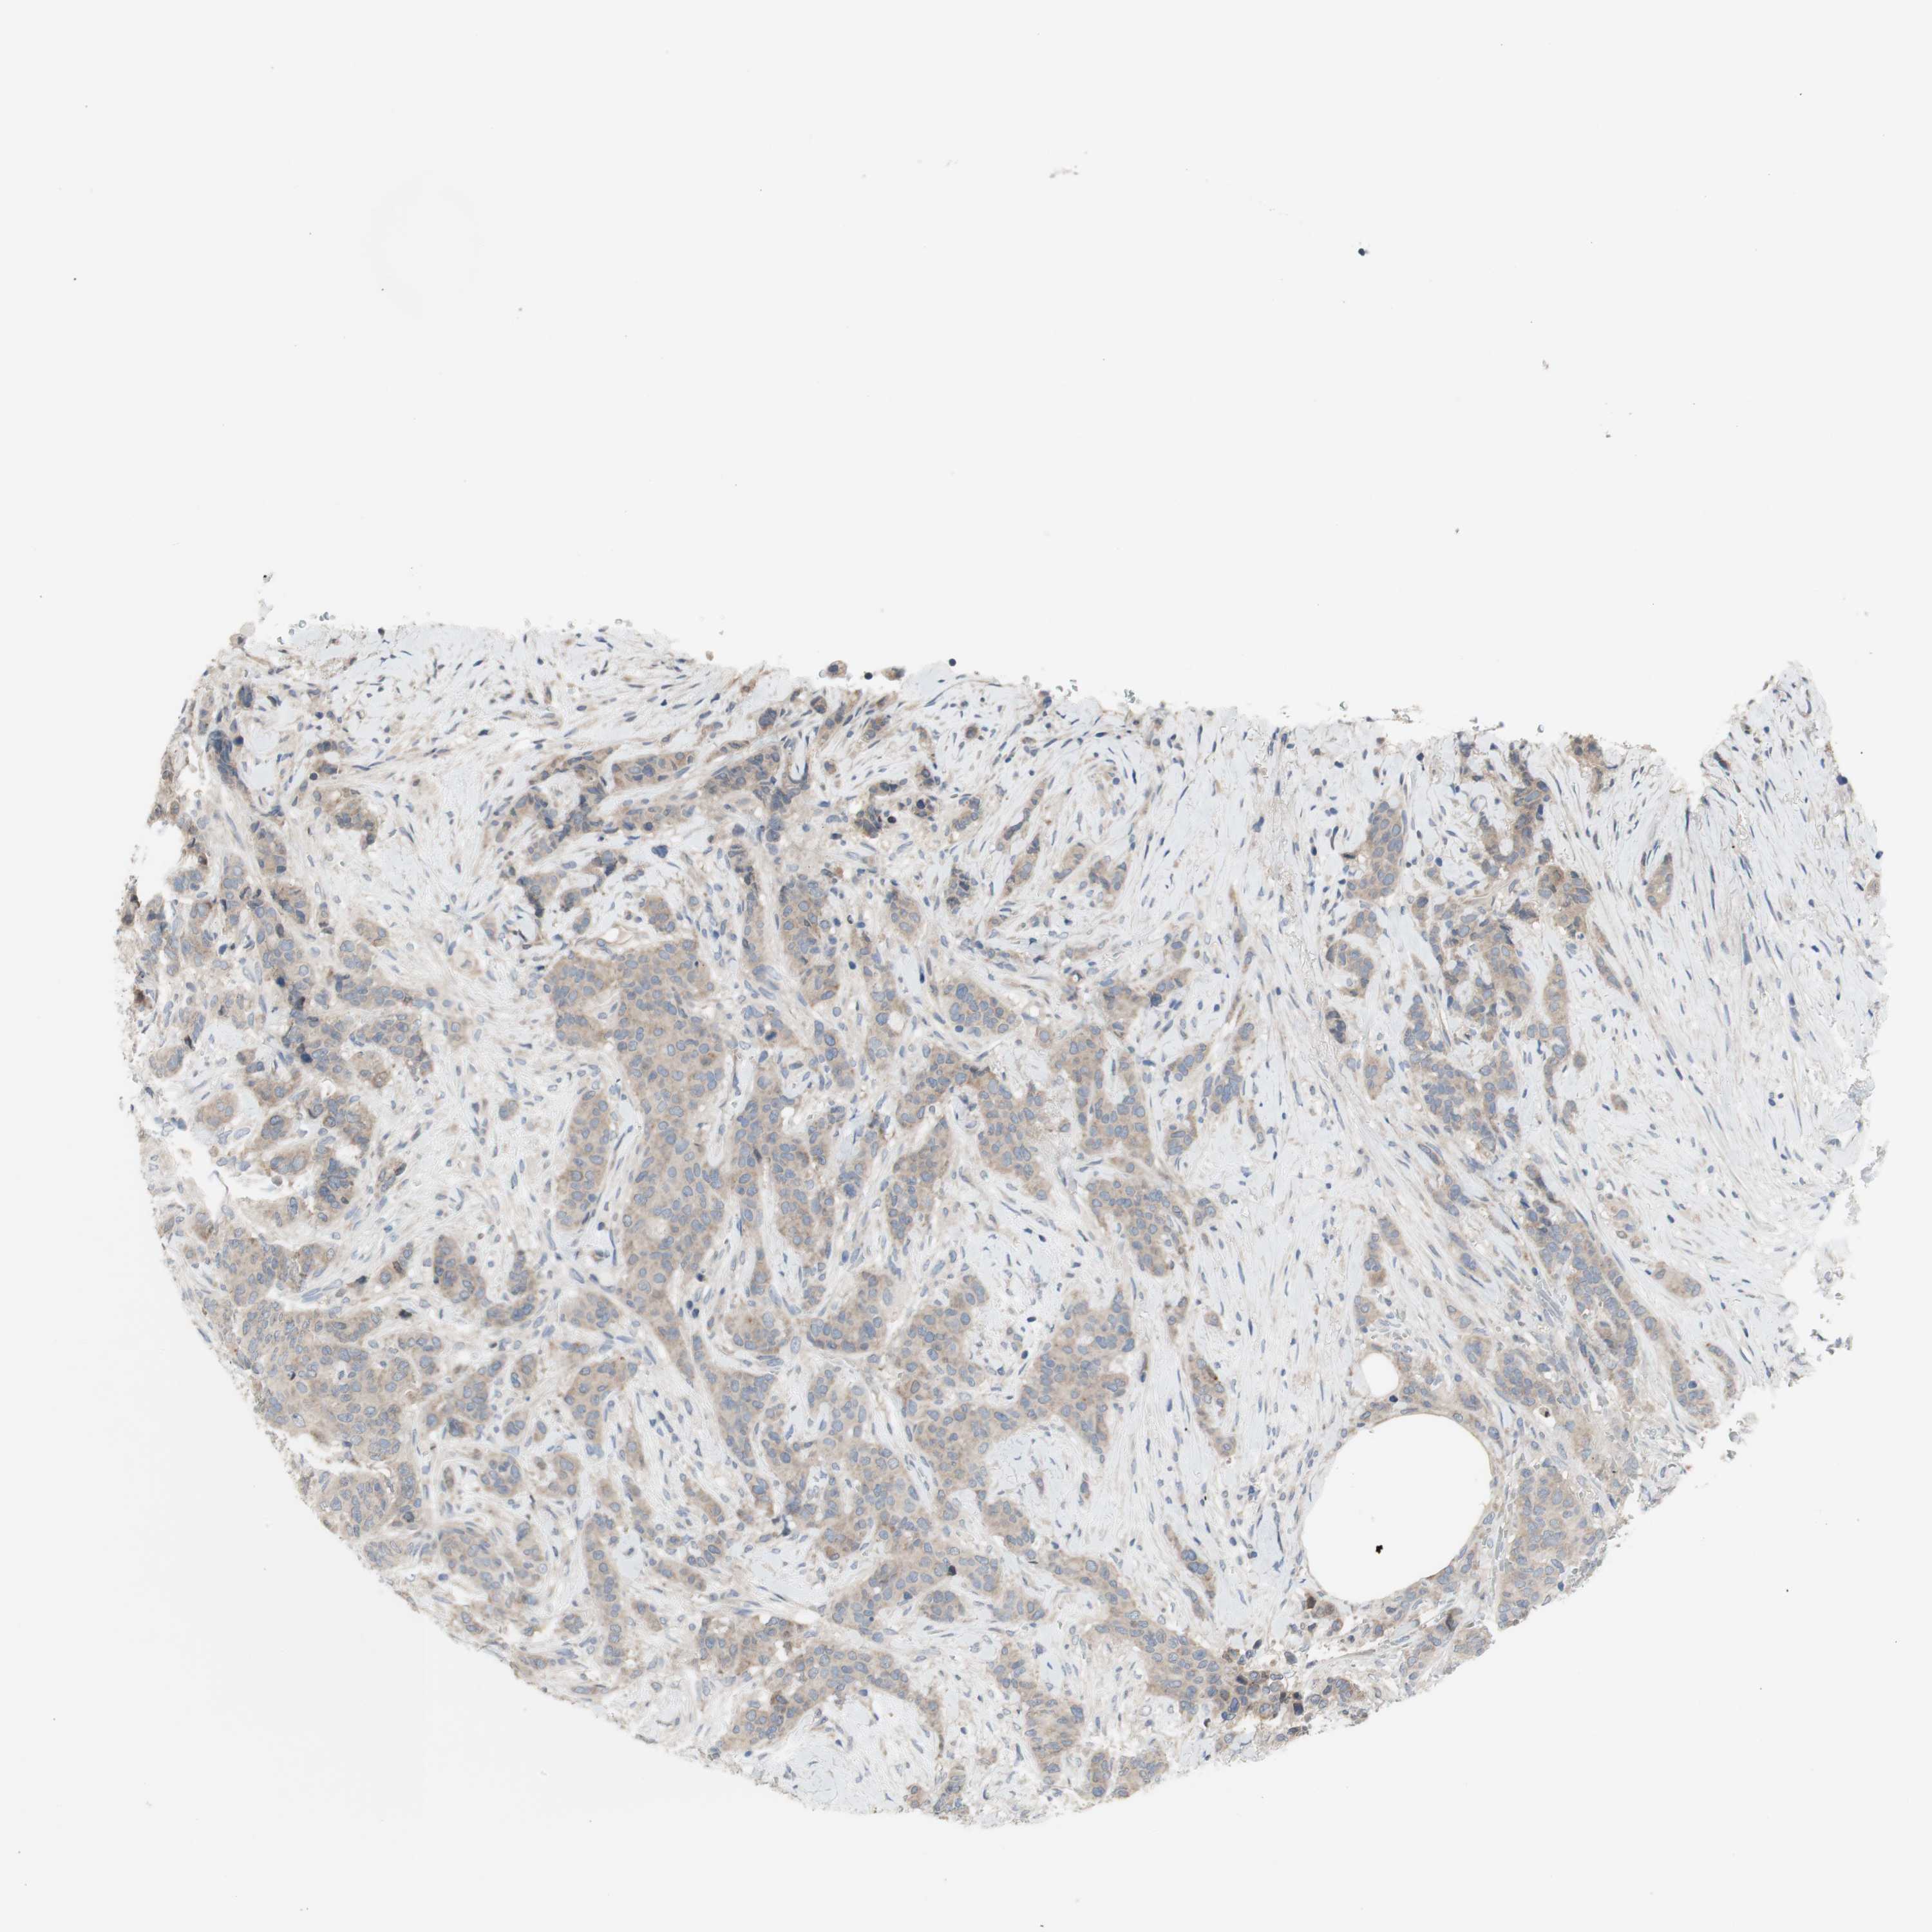

CANCER BREAST CANCER Show tissue menu

BRCA TCGA BRCA VALIDATION PROTEIN EXPRESSION